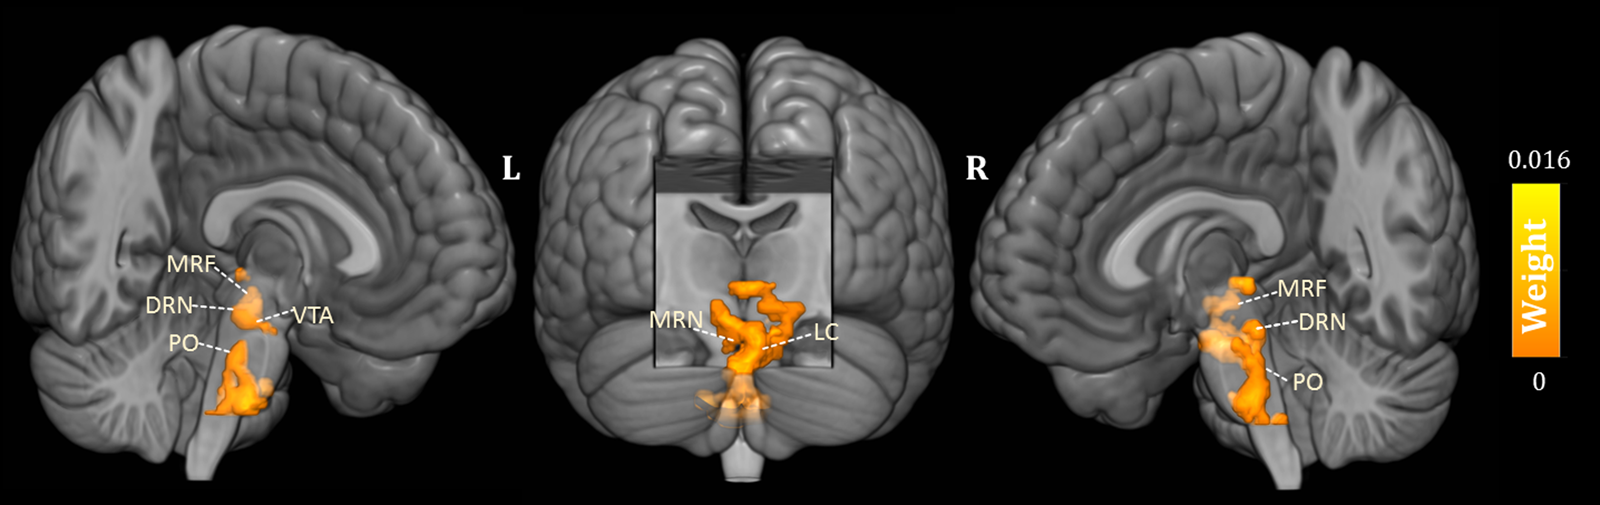

As shown in Fig. 1, the predicted RD scores significantly correlated with the actual RD scores (r = 0.425, p = 0.004; rMSE = 3.418, p = 0.015). Contributing to the predictions of RD, the MKL regression identified metabolic activity in the pontine nuclei (PO) and LC, the medial reticular formation (MRF), the dorsal/median raphe nuclei, the VTA, red nucleus, and substantia nigra [Fig. 2, only those voxels that survived at CV procedure are reported, the spatial location is identified by AAL3 (Rolls, Huang, Lin, Feng, & Joliot, Reference Rolls, Huang, Lin, Feng and Joliot2020) and the Harvard Ascending Arousal Network Atlas (Edlow et al., Reference Edlow, Takahashi, Wu, Benner, Dai, Bu and Folkerth2012)]. In addition, the age, gender, and mean global CMRglc value also contribute to MKL prediction (4.64% of total weight). The voxel-wise correlations indicated that the metabolic activity in these regions was positively correlated with RD scores. In addition, brain stem CMRglc was not predictive for HA (r = 0.164, p = 0.115; rMSE = 8.34, p = 0.152) and NS (r = −0.122, p = 0.516; rMSE = 6.26, p = 0.533) scores.

Fig. 2. Three-dimensional overview of voxel-wise kernel weight in the brainstem for reward dependence (RD) prediction, with cluster size >10 voxels. The color represents the relative informativeness of different voxels. PO, pontine nuclei; LC, locus coeruleus; MRF, medial reticular formation; DRN, dorsal raphe nuclei; MRN, median raphe nuclei; VTA, the ventral tegmental area.

This is the first study applying the MKL algorithm to predict the individual differences in temperament scores based on brainstem metabolic activity in TRD. The MKL model was able to predict the individual scores on RD from the brainstem metabolic activity, but brainstem CMRglc was not predictive for the individual scores on HA and NS. More precisely, we found that individual differences in RD are closely linked to metabolic increases in the raphe nuclei, the PO/LC, and the VTA, respectively, suggesting the implication of the serotonergic, noradrenergic, and dopaminergic system. These findings provide additional support that, at least in our case in the treatment-resistant depressed state, this temperament dimension shows significant increased CMRglc in brainstem regions associated with different monoaminergic NT systems (Samochowiec et al., Reference Samochowiec, Rybakowski, Czerski, Zakrzewska, Stepien, Pelka-Wysiecka and Hauser2001). Indeed, research not always has found the association between temperaments and their respective theoretically NT systems, and it remains an open question whether specific individual traits can be attributed to only one monoaminergic system (Robbins, Reference Robbins2018).

According to Cloningers' theory of personality, the temperament dimension RD has been linked with noradrenergic activity (Cloninger et al., Reference Cloninger, Przybeck, Svrakic and Wetzel1994). Norepinephrine, in addition to its effects on sensory processing and waking behavior, it contributes to cognition, flexibility, and mnemonic processes, and dense noradrenergic innervations in the prefrontal cortical and hippocampal areas are thought to modulate these functions (Borodovitsyna, Flamini, & Chandler, Reference Borodovitsyna, Flamini and Chandler2017). The personality temperament RD has been related to the formation of conditioned signals of reward (Gerra et al., Reference Gerra, Zaimovic, Timpano, Zambelli, Delsignore and Brambilla2000) and may be implicated to maintain the behavior previously associated with reward (Bond, Reference Bond2001). Subjects with lower scores on RD are described as less sentimental and less socially attached; they generally are less dependent on the approval of others, and those with higher scores than average are clinically characterized as eager to help and please others (Hansenne et al., Reference Hansenne, Reggers, Pinto, Kjiri, Ajamier and Ansseau1999). Given that RD also reflects the maintenance of socially rewarded behavior, our 18FDG-PET findings in the LC and the pontine noradrenergic nuclei suggests that in the treatment-resistant state, this could be mediated by the noradrenergic system, reflecting behavioral flexibility in social contacts. Besides that pontine microbleeds in stroke may lead to depression (Tang et al., Reference Tang, Chen, Liang, Chu, Mok, Ungvari and Wong2013, Reference Tang, Liu, Chen, Abrigo, Chu, Mok and Wong2014), the PO are the largest of the precerebellar nuclei, providing the principal input to the cerebellum (Kratochwil, Maheshwari, & Rijli, Reference Kratochwil, Maheshwari and Rijli2017; Schwarz & Thier, Reference Schwarz and Thier1999). Not surprisingly that current evidence also points to an important role of the cerebellum in the processing of social behaviors (Adamaszek et al., Reference Adamaszek, D'Agata, Ferrucci, Habas, Keulen, Kirkby and Verhoeven2017).

It is of interest to note that metabolic activity in serotonergic and dopaminergic-related brainstem structures was also predictive for RD scores when clinically depressed. Serotonin is considered as a fundamental mediator of emotional, motivational, and cognitive aspects of reward representation (Kranz, Kasper, & Lanzenberger, Reference Kranz, Kasper and Lanzenberger2010). The increased CMRglc in the raphe nuclei is suggestive for the involvement of the serotonergic system in this temperament construct in the desire for social relationships (Gerretsen et al., Reference Gerretsen, Graff-Guerrero, Menon, Pollock, Kapur, Vasdev and Mamo2010). It encodes reward probability, reward value and cost, and how beneficial the current environmental context may be (Luo, Li, & Zhong, Reference Luo, Li and Zhong2016). Besides that the dorsal raphe nucleus (DRN), the largest serotonergic nucleus in the brainstem, strongly moderates reinforcement learning, its neuronal activity has been associated with reward size (Nagai et al., Reference Nagai, Takayama, Nishitani, Andoh, Koda, Shirakawa and Kaneko2020) and reward waiting (Luo, Zhou, & Liu, Reference Luo, Zhou and Liu2015). Together with the medial raphe nuclei (MRN), the DRN modulates dopaminergic activity in the VTA, a region which has been primarily implicated in reward-motivated behavior, similar to the red nucleus and the substantia nigra (Browne et al., Reference Browne, Abela, Chu, Li, Ji, Lambe and Fletcher2019; Cha et al., Reference Cha, Carlson, Dedora, Greenberg, Proudfit and Mujica-Parodi2014). Of interest, it is the interaction between the serotonergic and the dopaminergic system that controls the behavioral response to reward (or punishment) (Macoveanu, Reference Macoveanu2014), potentially mediated by excitatory glutamatergic neurons (Wang et al., Reference Wang, Zhang, Qi, Wang, Cachope, Mejias-Aponte and Morales2019).

Although we only have focused on brainstem CMRglc, the positive relationship between RD scores and several specific brainstem areas associated with specific monoaminergic NT involvement suggest that, at least in the TRD state, the temperament RD construct goes beyond the noradrenergic system. This assumption is partly supported by the predictive metabolic activity of RD in the MRF, a medial brainstem network part of the emotional motor system mediated by multiple NT systems, also moderating emotional arousal and maintenance of consciousness (Venkatraman et al., Reference Venkatraman, Edlow and Immordino-Yang2017). Because we only measured CMRglc and no specific monoaminergic system, we can only assume that the higher metabolic activity predictive for higher scores on RD may represent higher order reward-related behavior and is mediated by noradrenaline, serotonin, and dopamine.